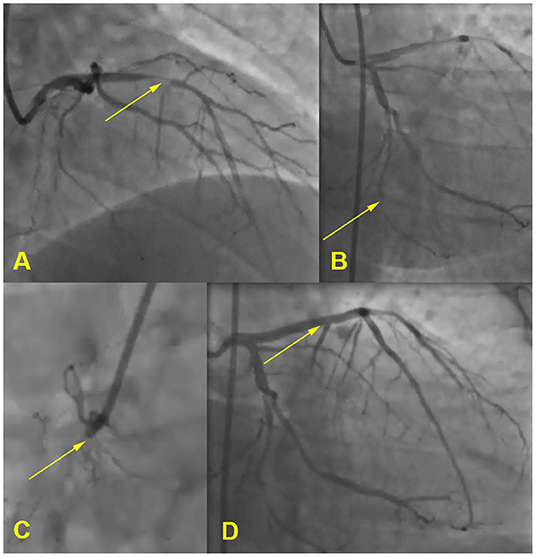

Electrocardiography showed sinus rhythm with Q-waves in leads III, aVF. A transthoratic echocardiogram was notable for an akinesis of basal and middle segments of inferior wall and a mild hypertrophy of the left ventricle. Coronary arteriography demonstrated the three-vessel disease: 80% occlusion of the proximal anterior descending artery, 85% occlusion of the distal circumflex artery, and 100% occlusion of the proximal right coronary artery. He received a drug eluting stent in anterior descending artery (see Figure 2). Duplex sonography revealed 40% stenosis of both femoral arteries, 50% stenosis of both superficial femoral arteries, and stenosis of carotid bifurcations and proximal internal carotid arteries up to 40% on the right and 50–55% on the left.

Figure 2. Coronary angiogram. (A) 80% occlusion of the proximal anterior descending artery, (B) 85% occlusion of the distal circumflex artery, (C) 100% occlusion of the proximal right coronary artery, (D) stent in anterior descending artery.